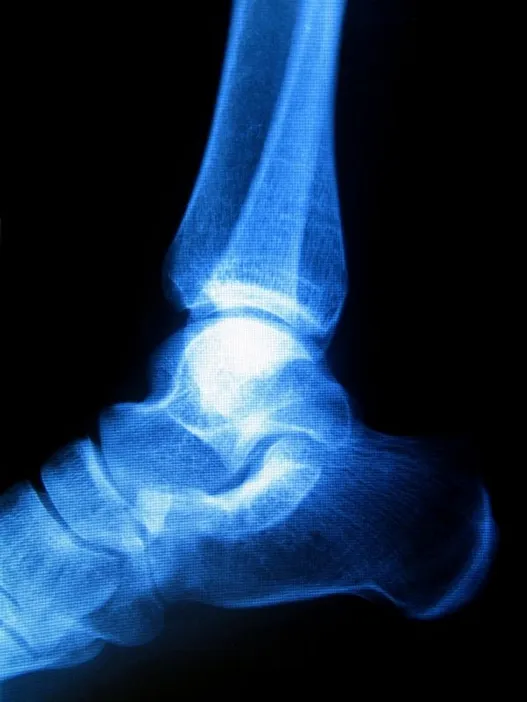

Haglund's Deformity

Sometimes known as “pump bump” because of its prevalence among women who wear pump-style shoes, Haglund's deformity can occur in one or both of the feet. If you are suffering from Haglund's deformity you will most likely have noticed a bony enlargement at the back of the heel. This inflammation is caused when the bursa, a fluid­ filled sac between the Achilles tendon and your heel bone, becomes irritated. Other signs of Haglund's deformity include pain where the Achilles tendon and the heel meet, swelling, and redness.